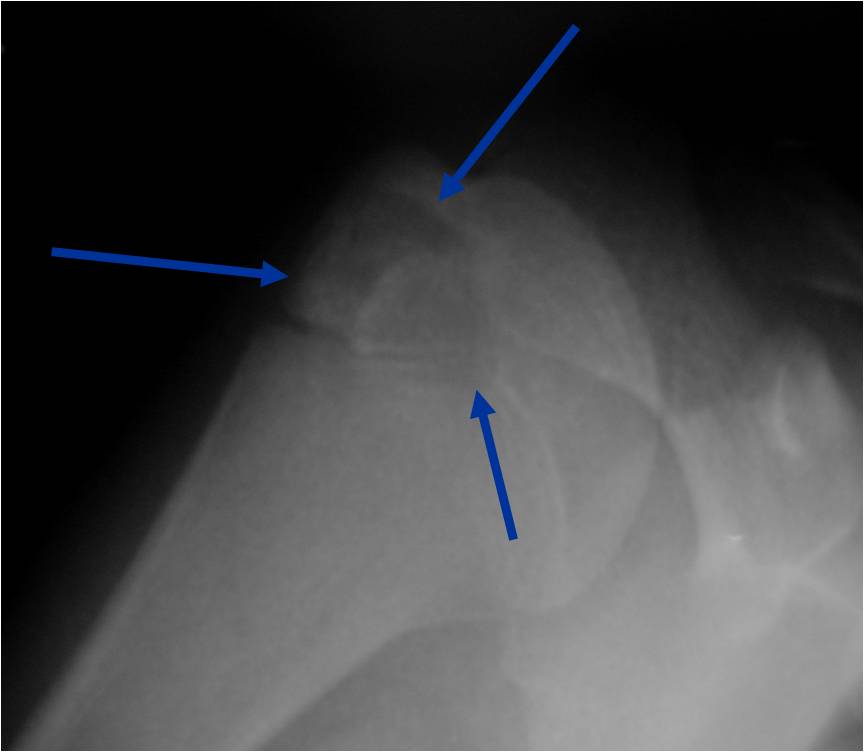

General Information Enchondroma is a benign indolent intramedullary hyaline cartilage neoplasm Accounts for 10% of all benign osseous tumors Limited growth, most lesions are less than 5 cm in maximal dimension Bones grow from a cartilaginous growth plate that...